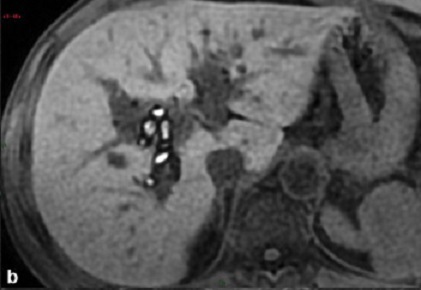

Image TDM

et IRM : Image radiologique

TDM et IRM de cholangite infectueuse c'est :

- La rehaussement nonhomogen de densite du

foie en phase arterielle du CT ,

- Image de dilatation des voies biliaire intra

hepatique ( peut etre central 38% , diffuse

16%,et segmentaire 46% ),

- Une dilatation de la voie biliaire

principale

- Une epaissisement parietal regulier et

systemique des voies biliaires ( superieure a

1.5mm d'epaisseur pour la voie biliaire

principale )

- Une prise de contrast homogene et precoce

des voies biliaires inflammatoires

Aspects arrondies

hypodensite a bord irregulier de deux abces

angiocholite situe du foie droit (

fleche rouge ) . Image radiologique TDM avec

de contrast intraveineuse ( C+ ) en coupe

axiale . |

|

Image d'une pyleplebite de veine

mesenterique supperieure ( fleche jaune ) .

Sa paroi est epais et hyperdensite

etre en vue tres nette ( fleche jaune ) sur ce coupe . Image radiologique TDM en coupe

coronal ( frontal ) |